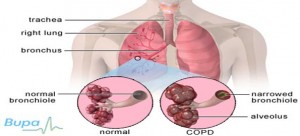

3. ХОЗЛ - Хронічна обструктивна хвороба легень 6%

Причини: Куріння, Вдихання шкідливих газів, Брудне повітря